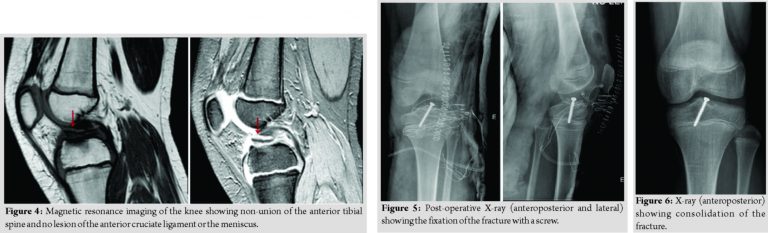

A 47-year-old Caucasian female, trader, with no relevant medical history, presented to the emergency department for pain in the proximal third of the left forearm, of sudden onset, intense, after movement of pronation, without a history of traumatism. She had no fever, no inflammatory signs, but she had pain on the palpation of the proximal radius and limitation of the active and passive mobilities. The radiographs of the elbow and forearm showed a pathological fracture of the proximal radius associated with lytic lesion (Fig. 1). Computed tomography (CT) scan of the left elbow showed “lytic lesion, with 57 × 18 mm, reduction and fragmentation of cortical thickness –a pathological fracture; without suspected reaction of the periosteum” (Fig. 2).

An immobilization of the left arm and forearm was performed. The magnetic resonance imaging of the left forearm revealed “primary bone lesion without invasive features of the soft tissues that can correspond to aneurysmal bone cyst or GCT” (Fig. 3). A biopsy and surgery were proposed. The patient underwent excision and curettage of the lesion with preservation of the periosteum, filling with the left proximal (corpse) allograft and osteosynthesis with plate and screws (Fig. 4).

The anatomopathological examination revealed characteristics compatible with GCT of bone (Fig. 5). The surgery was uneventful and there was no neurovascular injury. The post-operative period was also uneventful. During follow-up, a good clinical and radiological evolution was observed, with consolidation of the lesion (Fig. 6) and recovery of the arch of mobility of the elbow, presenting a deficit of 15° of supination compared to the contralateral side. There was no local recurrence of the lesion and there was no metastization in 2 years of follow-up.